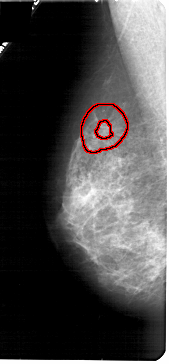

FILE: A_1790_1.LEFT_MLO.OVERLAY

TOTAL_ABNORMALITIES 1

ABNORMALITY 1

LESION_TYPE MASS SHAPE IRREGULAR MARGINS SPICULATED

ASSESSMENT 4

SUBTLETY 1

PATHOLOGY MALIGNANT

TOTAL_OUTLINES 2

BOUNDARY

CORE